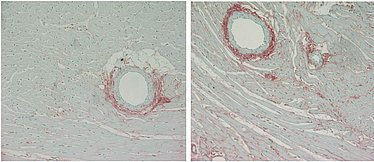

Ein weiterer Schwerpunkt unseres Interesses ist die Aufklärung der Funktion der alpha8 Integrinkette in glatten Muskelzellen (VSMC) Proliferation, Adhäsion und Migration von VSMC tragen zu arteriosklerotischen Veränderungen der Gefäße bei. Integrine sind als Matrixrezeptoren an der Regulation dieser Vorgänge beteiligt. Eigene Vorbefunde zeigen, daß alpha8 Integrin spezifisch in VSMC exprimiert wird und das Ausmass der Gefäßläsionen bei Atherosklerose und Hypertonie mit beeinflusst. Die Ergebnisse unserer Studien sollen zu einem besseren Verständnis der Pathomechanismen arteriosklerotischer Läsionen beitragen.

Marek I, Lichtneger T, Cordasic N, Hilgers KF, Volkert G, Fahlbusch F, Rascher W, Hartner A, Menendez-Castro C (2016): Alpha8 integrin signalling attenuates chronic renal interstitial fibrosis by reducing fibroblast activation, not by interfering with the regulation of cell turnover. PLoS One 11, e0150471

Menendez-Castro C, Cordasic N, Neureiter D, Amann K, Marek I, Volkert G, Stintzing S, Jahn A, Rascher W, Hilgers KF, Hartner A (2015): Underexpression of alpha8 integrin aggravates experimental atherosclerosis. J Pathol 236, 5-16